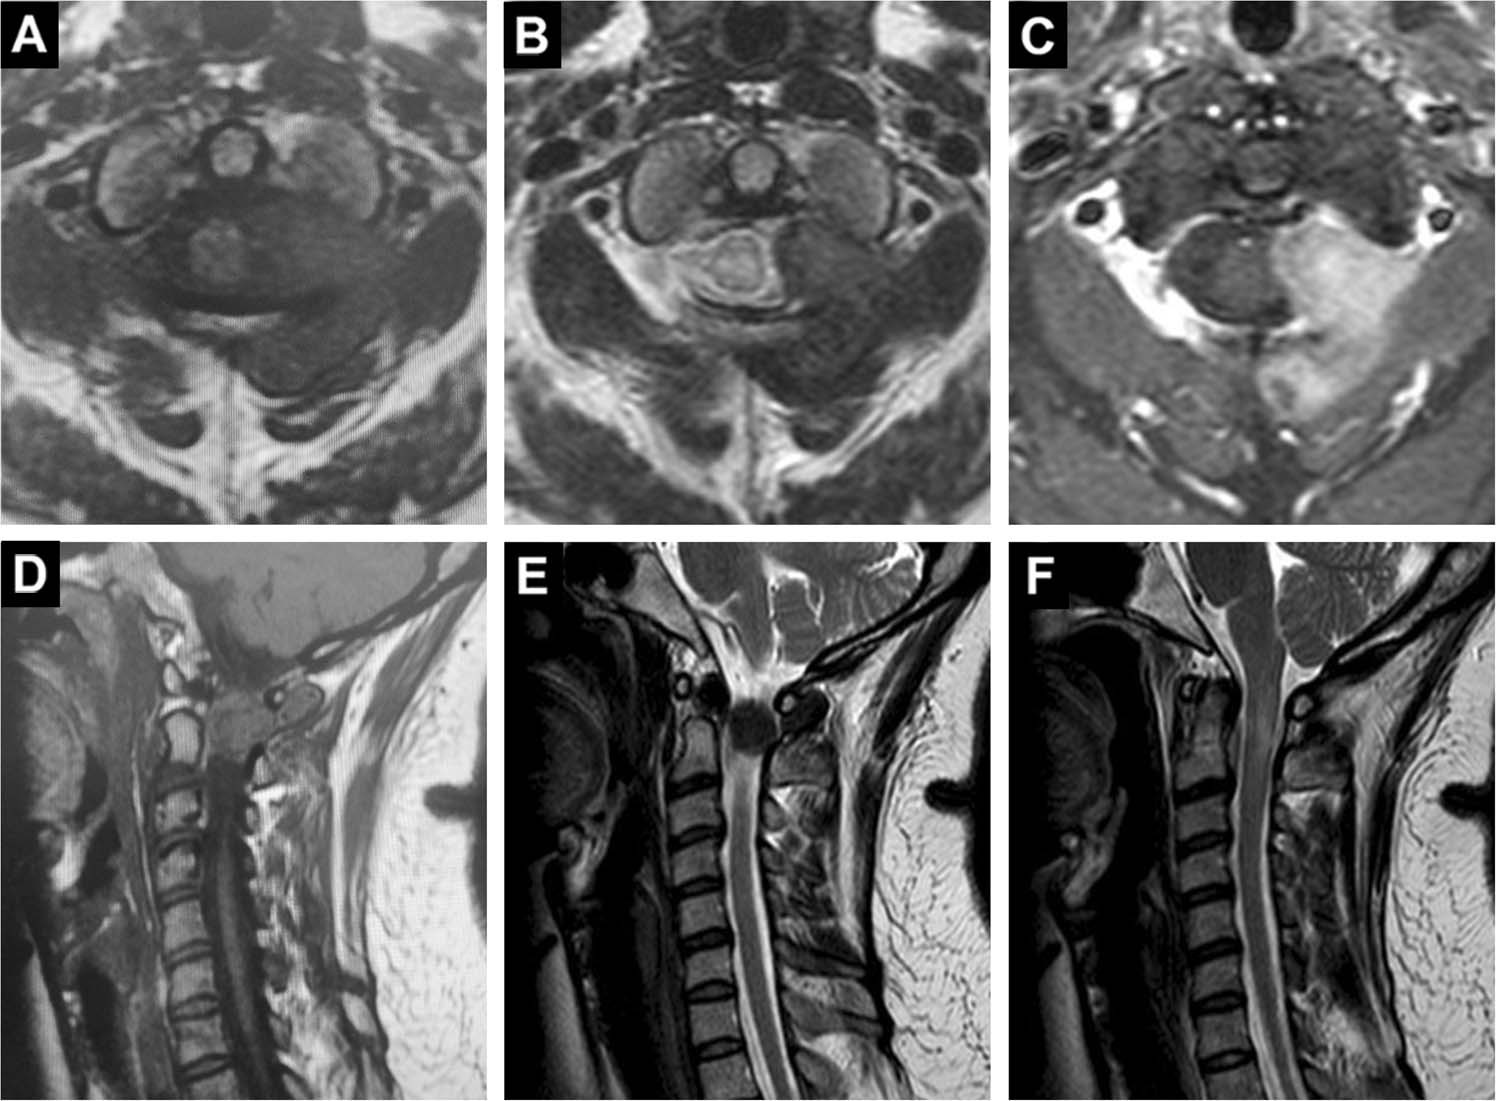

Tenosynovial giant cell tumor involving the cervical spine: A case report

image size: 1920x591